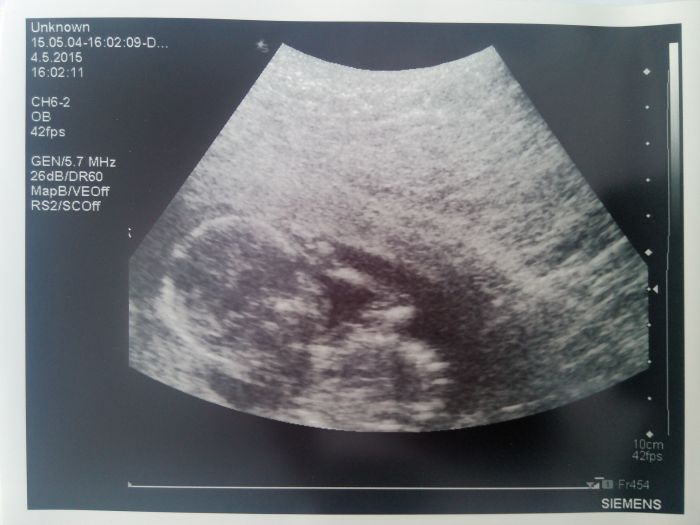

Ahoj devcatka :) dnes jsem byla na ultrazvuku v 16+2... Dle ultrazvuku dohanime ten nas 3tydenni rozdil mezi terminy porodu na 16+6 aspon neco :)) podle ms 19+2 :-D..zitra jdu na odber krve a doufam ze nebude falesne pozitiv.vysledek :(... Mimi se ma cile k svetu ..cely ultrazvuk nam mávalo :))) a uz mam zadanku na ultrazvuk 20tt tak se musim zitra objednat :-)... Musim vas docist..byla jsem tu snad naposledy v patek ;)